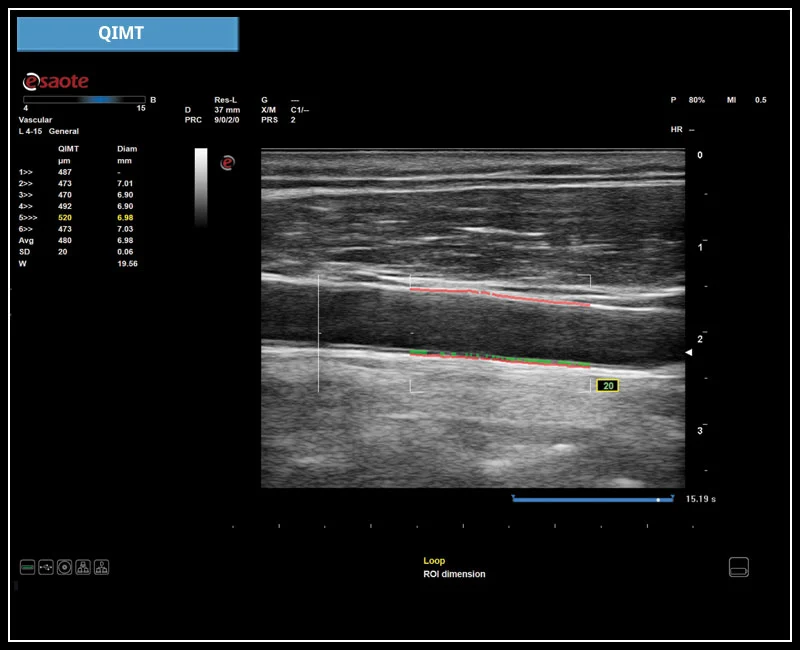

MyLab™X5 - QIMT

MyLab™X5 - QIMT